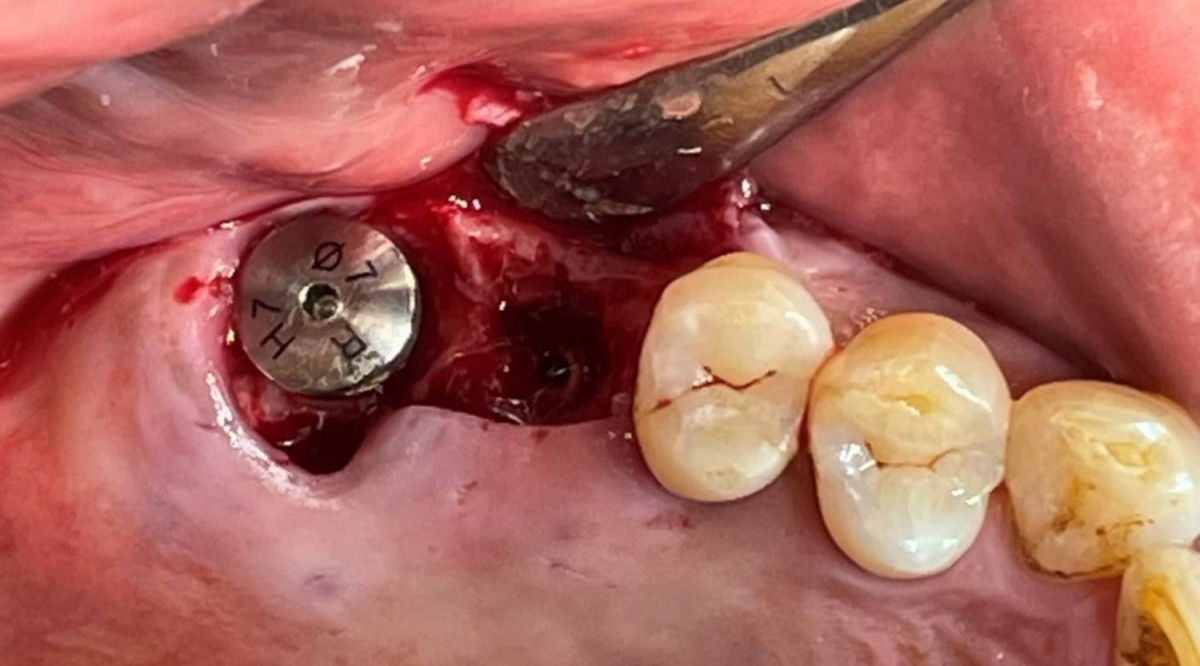

Maxillary Sinus Graft, 2 Implants, Crown Contouring

<GCaks> A 56-year-old male patient had pain-inducing caries, and perio-involved tooth mobility resulted in a tooth fracture at 1st molar. And it was removed months ago. He was a heavy smoker and showed poor oral hygiene.